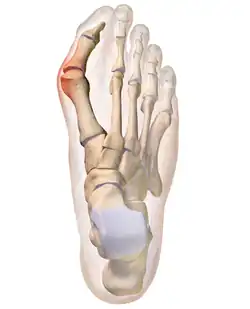

Drawing of a bunion

A bunion, also known as hallux valgus, is an outward deformity of the foot's metatarsophalangeal (MTP) joint which connects the big toe to the foot.[2] The rear tarsametatarsal joint that holds the metatarsal bone in a straight-ahead position weakens, the metatarsal moves outward plus rotates 90 degrees bringing the sesamoids up against the adjacent toe. This results in the head of the metatarsal bulging outward, and the big toe then bends inward toward the other toes. The joint often becomes red and painful due to rubbing in a cramped shoe.[2] The onset of bunions is typically gradual.[2] Joint complications may include bursitis or arthritis.[2] A similar condition of the little toe is referred to as a bunionette.[2]

The bump itself is due to the head of the metatarsal partly due to the swollen bursal sac or an osseous (bony) anomaly on the metatarsophalangeal joint. The larger part of the bump is a normal part of the head of the first metatarsal bone that has tilted sideways to stick out at its distal (far) end (metatarsus primus varus).

Bunions are commonly associated with a deviated position of the big toe toward the second toe, and the deviation in the angle between the first and second metatarsal bones of the foot. The small sesamoid bones found beneath the first metatarsal (which help the flexor tendon bend the big toe downwards) may also become deviated over time as the first metatarsal bone drifts away from its normal position. Osteoarthritis of the first metatarsophalangeal joint, diminished or altered range of motion, and discomfort with pressure applied to the bump or with motion of the joint, may all accompany bunion development. Atop of the first metatarsal head either medially or dorso-medially, there can also arise a bursa that when inflamed (bursitis), can be the most painful aspect of the process.